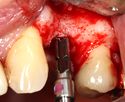

يتم اجراء جراحة الأسنان في العيادة تحت ظروف معقمة، من قبل طبيب أسنان متخصص في زراعة الأسنان و/أو جراحة الفم والفك. يتم تخدير المريض بواسطة حقنة بمخدر موضعي في منطقة دواعم السن، كما هو الحال في علاجات الأسنان العادية (في بعض الأحيان هناك حاجة بتوسيع نطاق التخدير، وفقاً لموقع الغرسات).

اذا كان العظم على استعداد لتلقي الزرع (أحيانا بعد سلسلة علاجات مسبقة)، يمكن البدء بعملية زرع الاسنان. يتم تثبيت المسامير المعدنية اللولبيه براغي، بعظم الفك. في سلسلة اخرى من العلاجات بعد فترة من ادخال البراغي، تبدا عمليات اعادة البناء عن طريق أخذ القياسات وانشاء التاج/الجسر. عندما يدور الحديث عن فترة الانتظار بين تركيب الغرسات وبين تنفيذ الاستبناء النهائي، فان هنالك اكثر من نهج واحد. النهج المتبع غالبا هو الانتظار لمدة 6 أسابيع على الأقل حتى تلتئم الانسجة، وأحيانا تصل فترة الانتظار لعدة شهور.